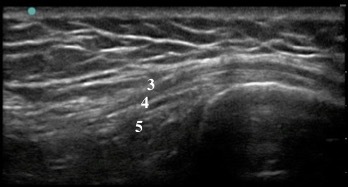

Knee Pes Anserine Long Axis 2 Image